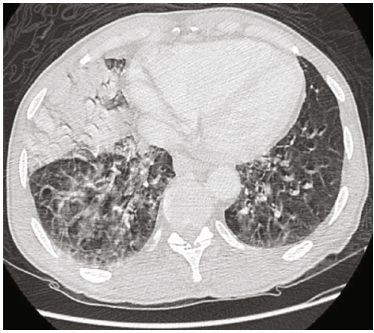

患者就诊时体温为98.8华氏度,血压为143/82mmHg,心率为84bpm,呼吸频率为21bpm,室内空气中的氧饱和度为82%。呼吸系统检查显示双侧湿罗音,双侧空气进入不良。胸部CT显示双侧磨玻璃样阴影和右中叶实变(图1)。

图1